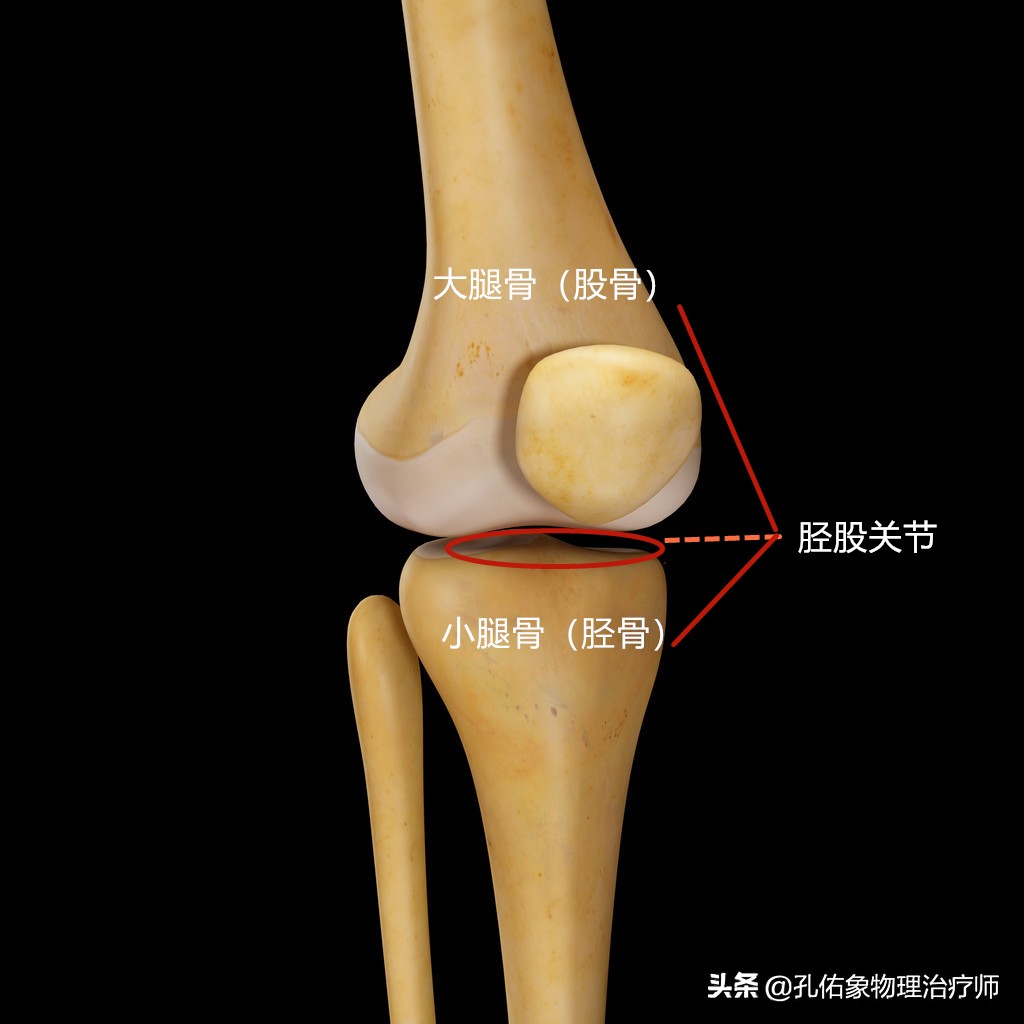

关节,就是两根骨头的连接。比如膝关节就是大腿骨和小腿骨之间的连接。从人体表面咋一看,膝关节就是一个单一的关节,可在医学专业人研究膝关节疼痛时,它并非是一个单一关节,而是由两个关节构成的一个复合关节。如下图所示:

胫股关节

构成人体膝关节复合体之一的关节,就是上图所示的大腿骨与小腿骨连接的胫股关节,若是拍片后,它是长这样的,看下图: